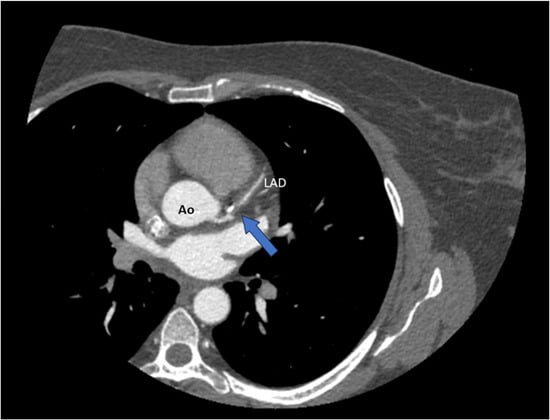

Advantages: CT angiography can detect characteristic features of SCAD, such as tapered luminal narrowing (a gradual reduction in vessel diameter over an extended segment), abrupt narrowing, non-plaque-related occlusions, intimal flaps, and intramural hematomas manifesting as wall thickening [] (Figure 4).

CT coronary angiography (CTCA) revealing a spontaneous dissection of the left anterior descending artery (LAD) (blue arrow). Ao = aorta.

It can also indirectly reveal pericoronary inflammation (perivascular edema/fat stranding) and excessive coronary tortuosity—features frequently associated with SCAD [,].